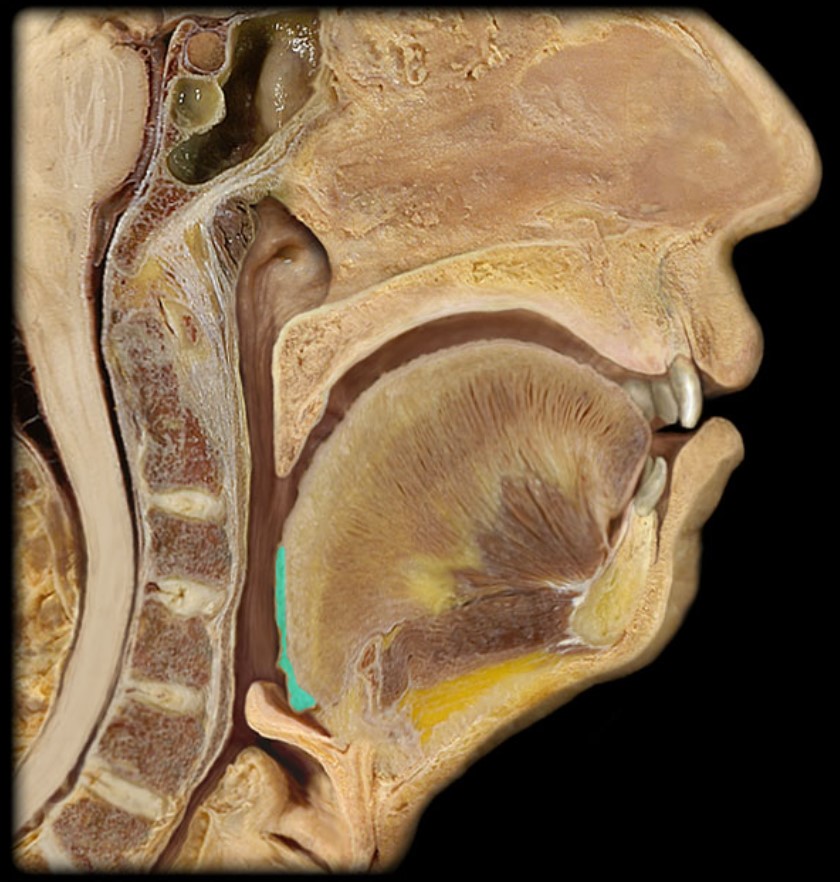

Esophagus

Trachea

Vocal Fold

Epiglottis

Hyoid

Mandible

Mylohyoid

Geniohyoid

Genioglossus

Lingual Tonsil

Palatine Tonsil

Uvula

Soft Palate